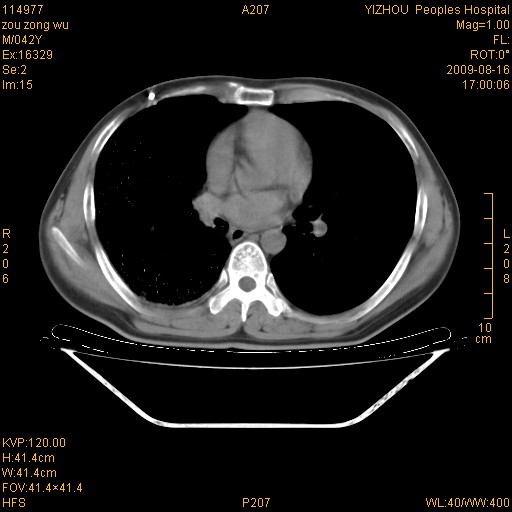

以下是引用zjzjr在2009-8-17 10:42:00的发言:[br]右侧间质性肺炎伴纤维化,右肺下叶肺囊肿伴感染(不除外外伤后引起),右肺野及胸壁软组织\\肝内见多发斑点状,中枪了吧.右侧胸膜肥厚\\粘连.